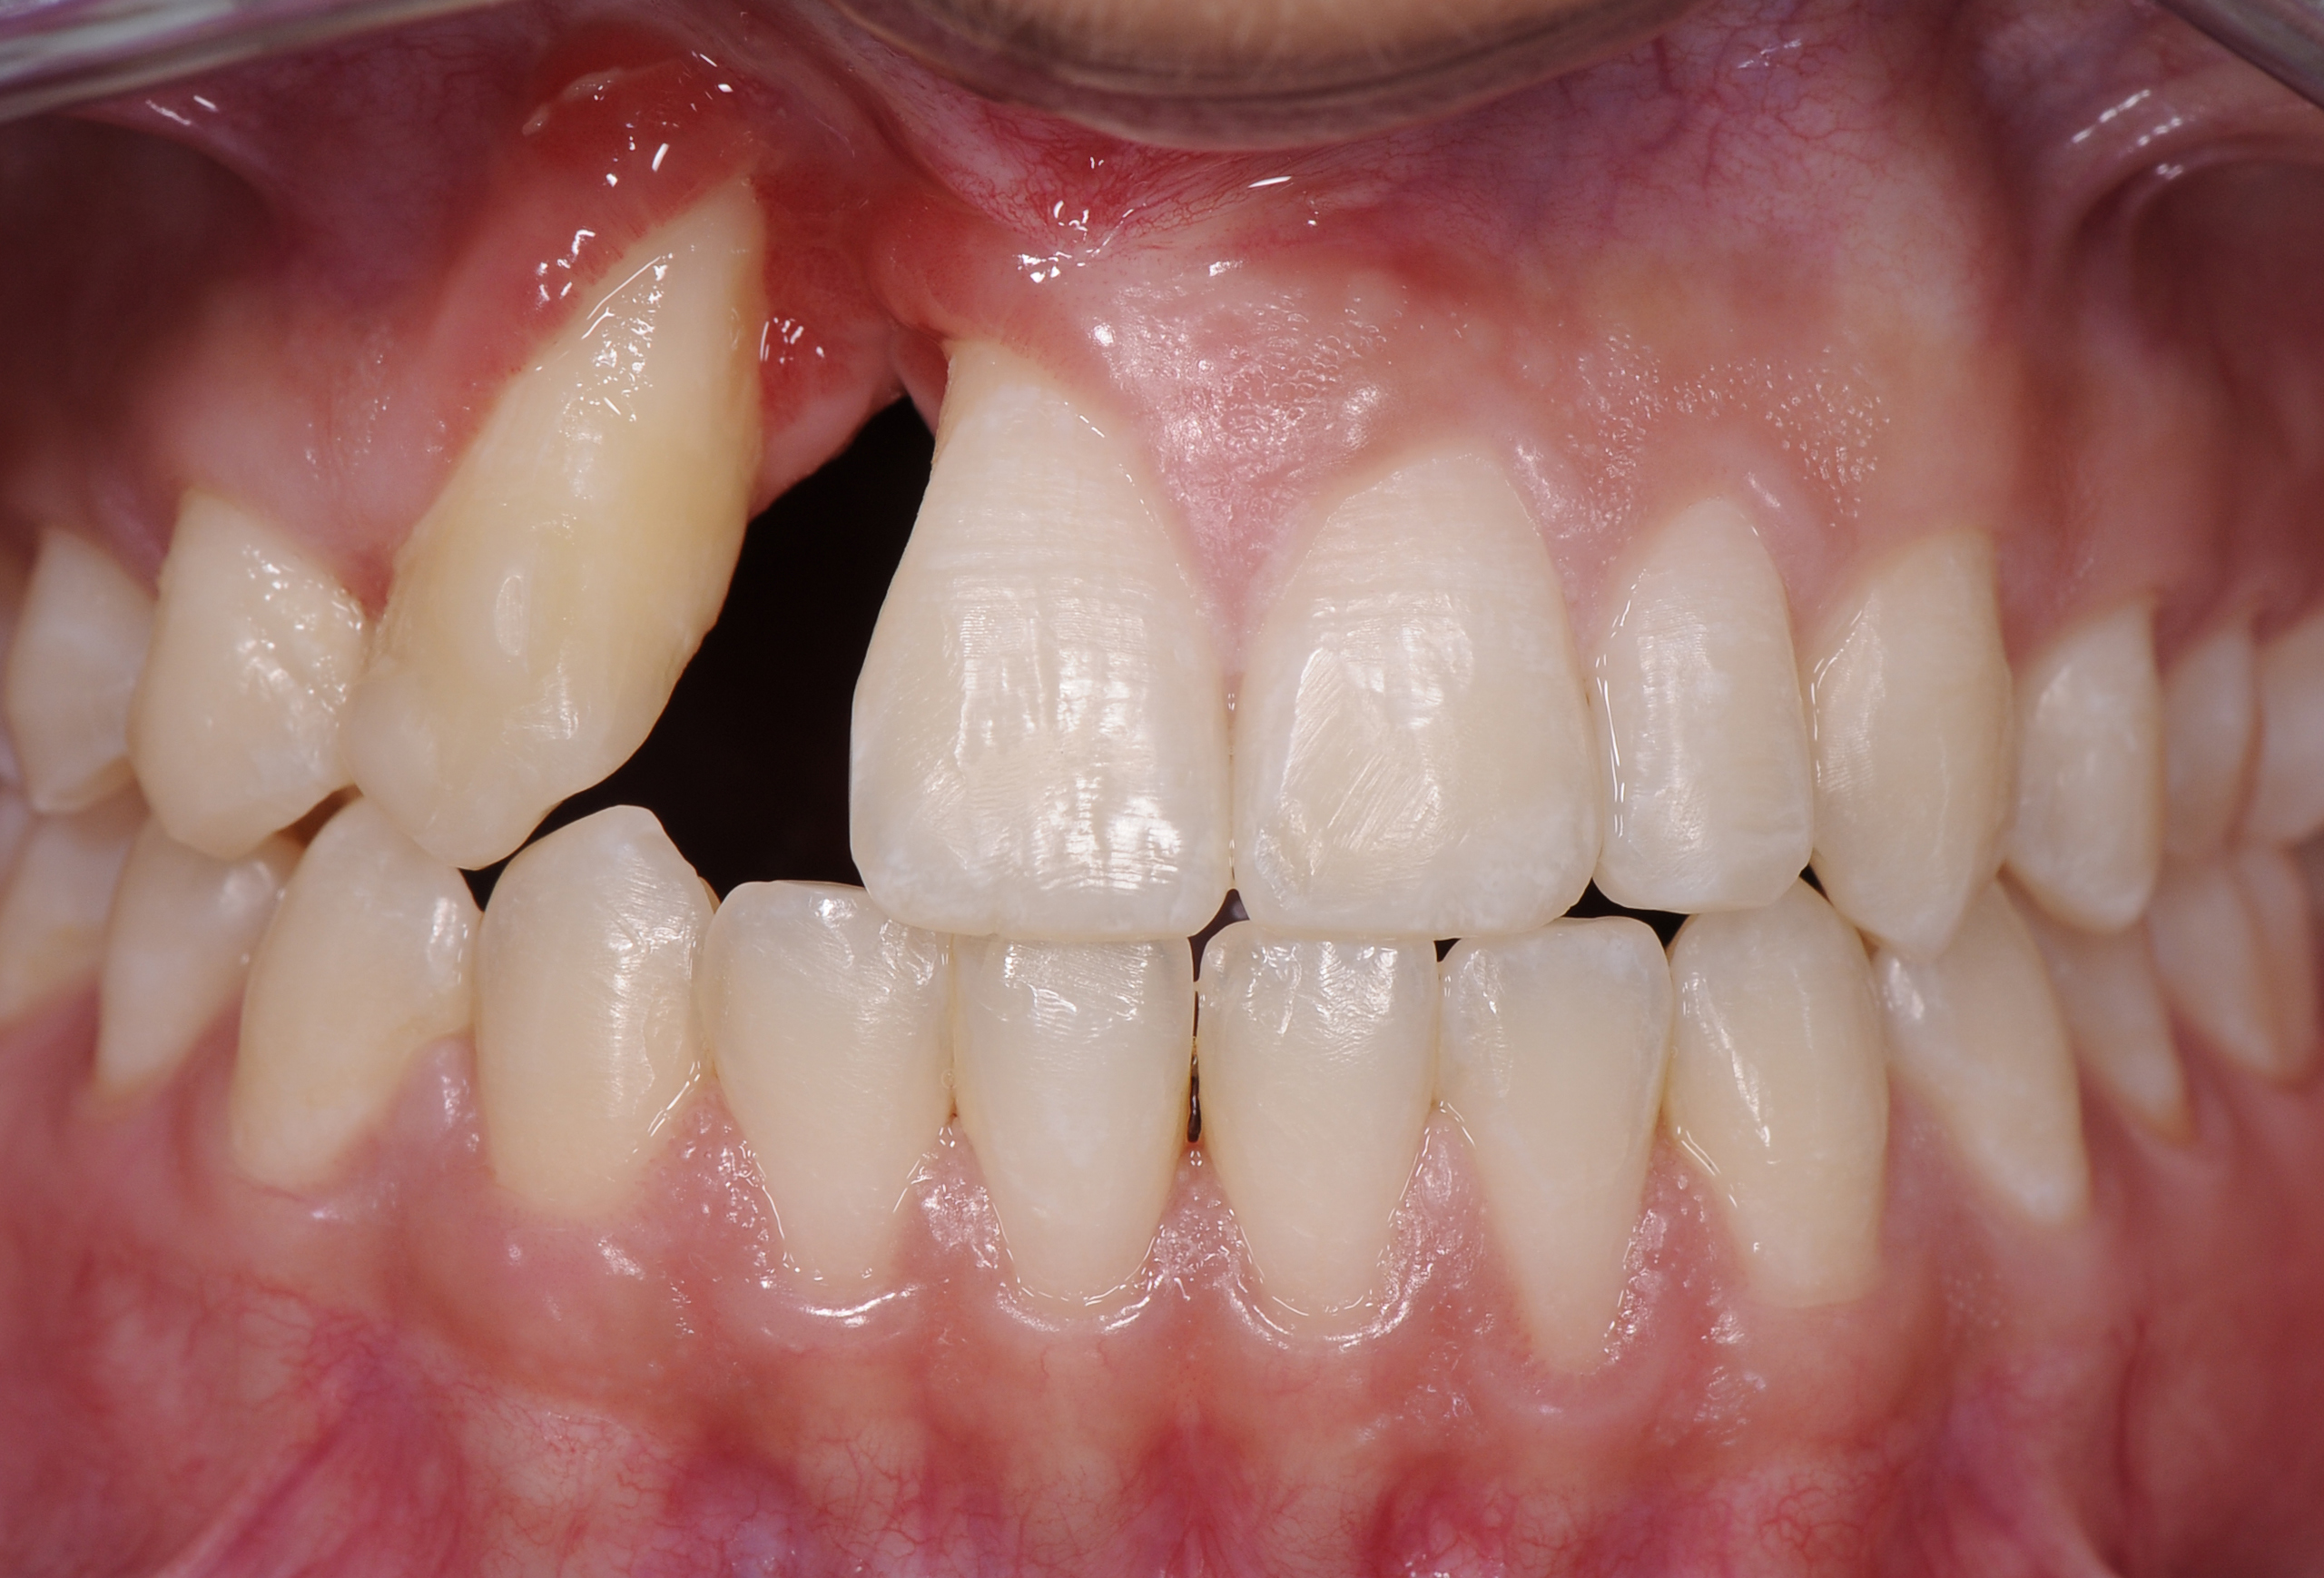

A healthy 20-year-old woman presented to the author’s office requesting treatment for a large defect in the area of missing tooth No. 7. She exhibited a high smile line that revealed a clearly visible deformity, associated with pain and sensitivity on teeth Nos. 6 and 8 and in the area of tooth No. 7 (Figure 1). Although the patient wore a modified Essix retainer, the defect was still visible because of the magnitude of tissue loss and the revealing nature of her smile.

The intraoral examination revealed a substantial deficit of alveolar bone and gingival tissues in the maxillary right lateral incisor area. The ridge defect exhibited vertical and horizontal components, which were associated with a severe loss of clinical attachment on both the mesial aspect of tooth No. 6 and the distal aspect of tooth No. 8. Although probing depths were within normal limits, minimal keratinized gingiva was present and the soft tissues were acutely inflamed. Plaque removal was difficult because of the soft-tissue defect, gingival-margin location, and irregular soft-tissue architecture. Additionally, bone sequestration could be observed through the labial mucosa (Figure 2).